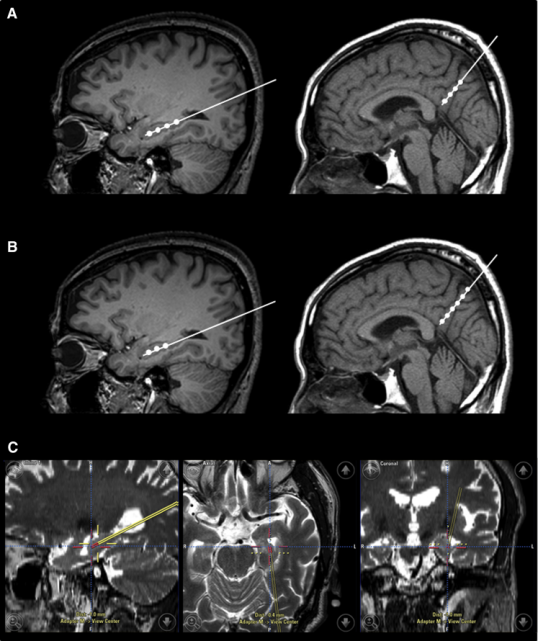

2015年,韓國首爾三星醫療中心招募了9名輕度至中度癡呆的阿爾茨海默氏病患者。Kim對9名患者進行了一項立體定向注射間充質干細胞的I期臨床試驗。

三名患者接受低劑量(1.0×107細胞/2 mL),6名患者接受高劑量(3.0×107hUCB-MSC 的細胞/2 mL) 。9名患者進行了三次干細胞注射(每隔4周一次)。

干細胞立體定向注射患者的右海馬體和右前丘盤

在之后長達36個月的跟蹤研究期間, 沒有患者出現嚴重的不良事件。由此可見, 干細胞治療阿爾茲海默癥是可行、安全且耐受性良好的。